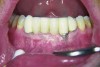

Geurs et al18 also found that establishing a soft-tissue barrier sheltered the underlying osseous structures and the osseointegration around the implant body. Kim et al19 conducted a study with 276 implants placed in 100 patients and demonstrated that cases with insufficient keratinized gingiva near the implants showed increased risk of gingival recession (Figure 8) and crestal bone loss. It is critical that keratinized tissue be evaluated around both teeth and implants, and when there is an insufficient amount, treatment should be considered to increase the thickness and overall health.

Fig 8. The implant on No. 23 4 years later with no maintenance care, showing increased inflammation and recession.

Figure 8